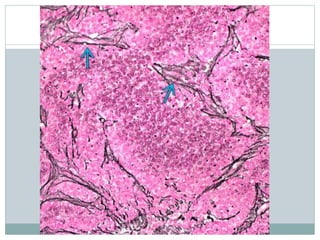

• #11 Ewing sarcoma (ES) is a highly cellular, high-grade sarcoma with a dense, solid to sheet-like distribution of cells, as depicted. Most tumors are diagnosed on small biopsy prior to treatment with chemotherapy, and large, preserved sections, as shown, are uncommon.

• #12 The tumor is classically very cellular cells arranged in diffuse sheets or lobules. Tumor cells and nuclei are generally uniform. Stromal vessels are commonly found.

• #13 This case of ES features a more prominent lobulated pattern of growth with large nests and sheets of clear tumor cells separated by thickened fibrocollagenous septa .